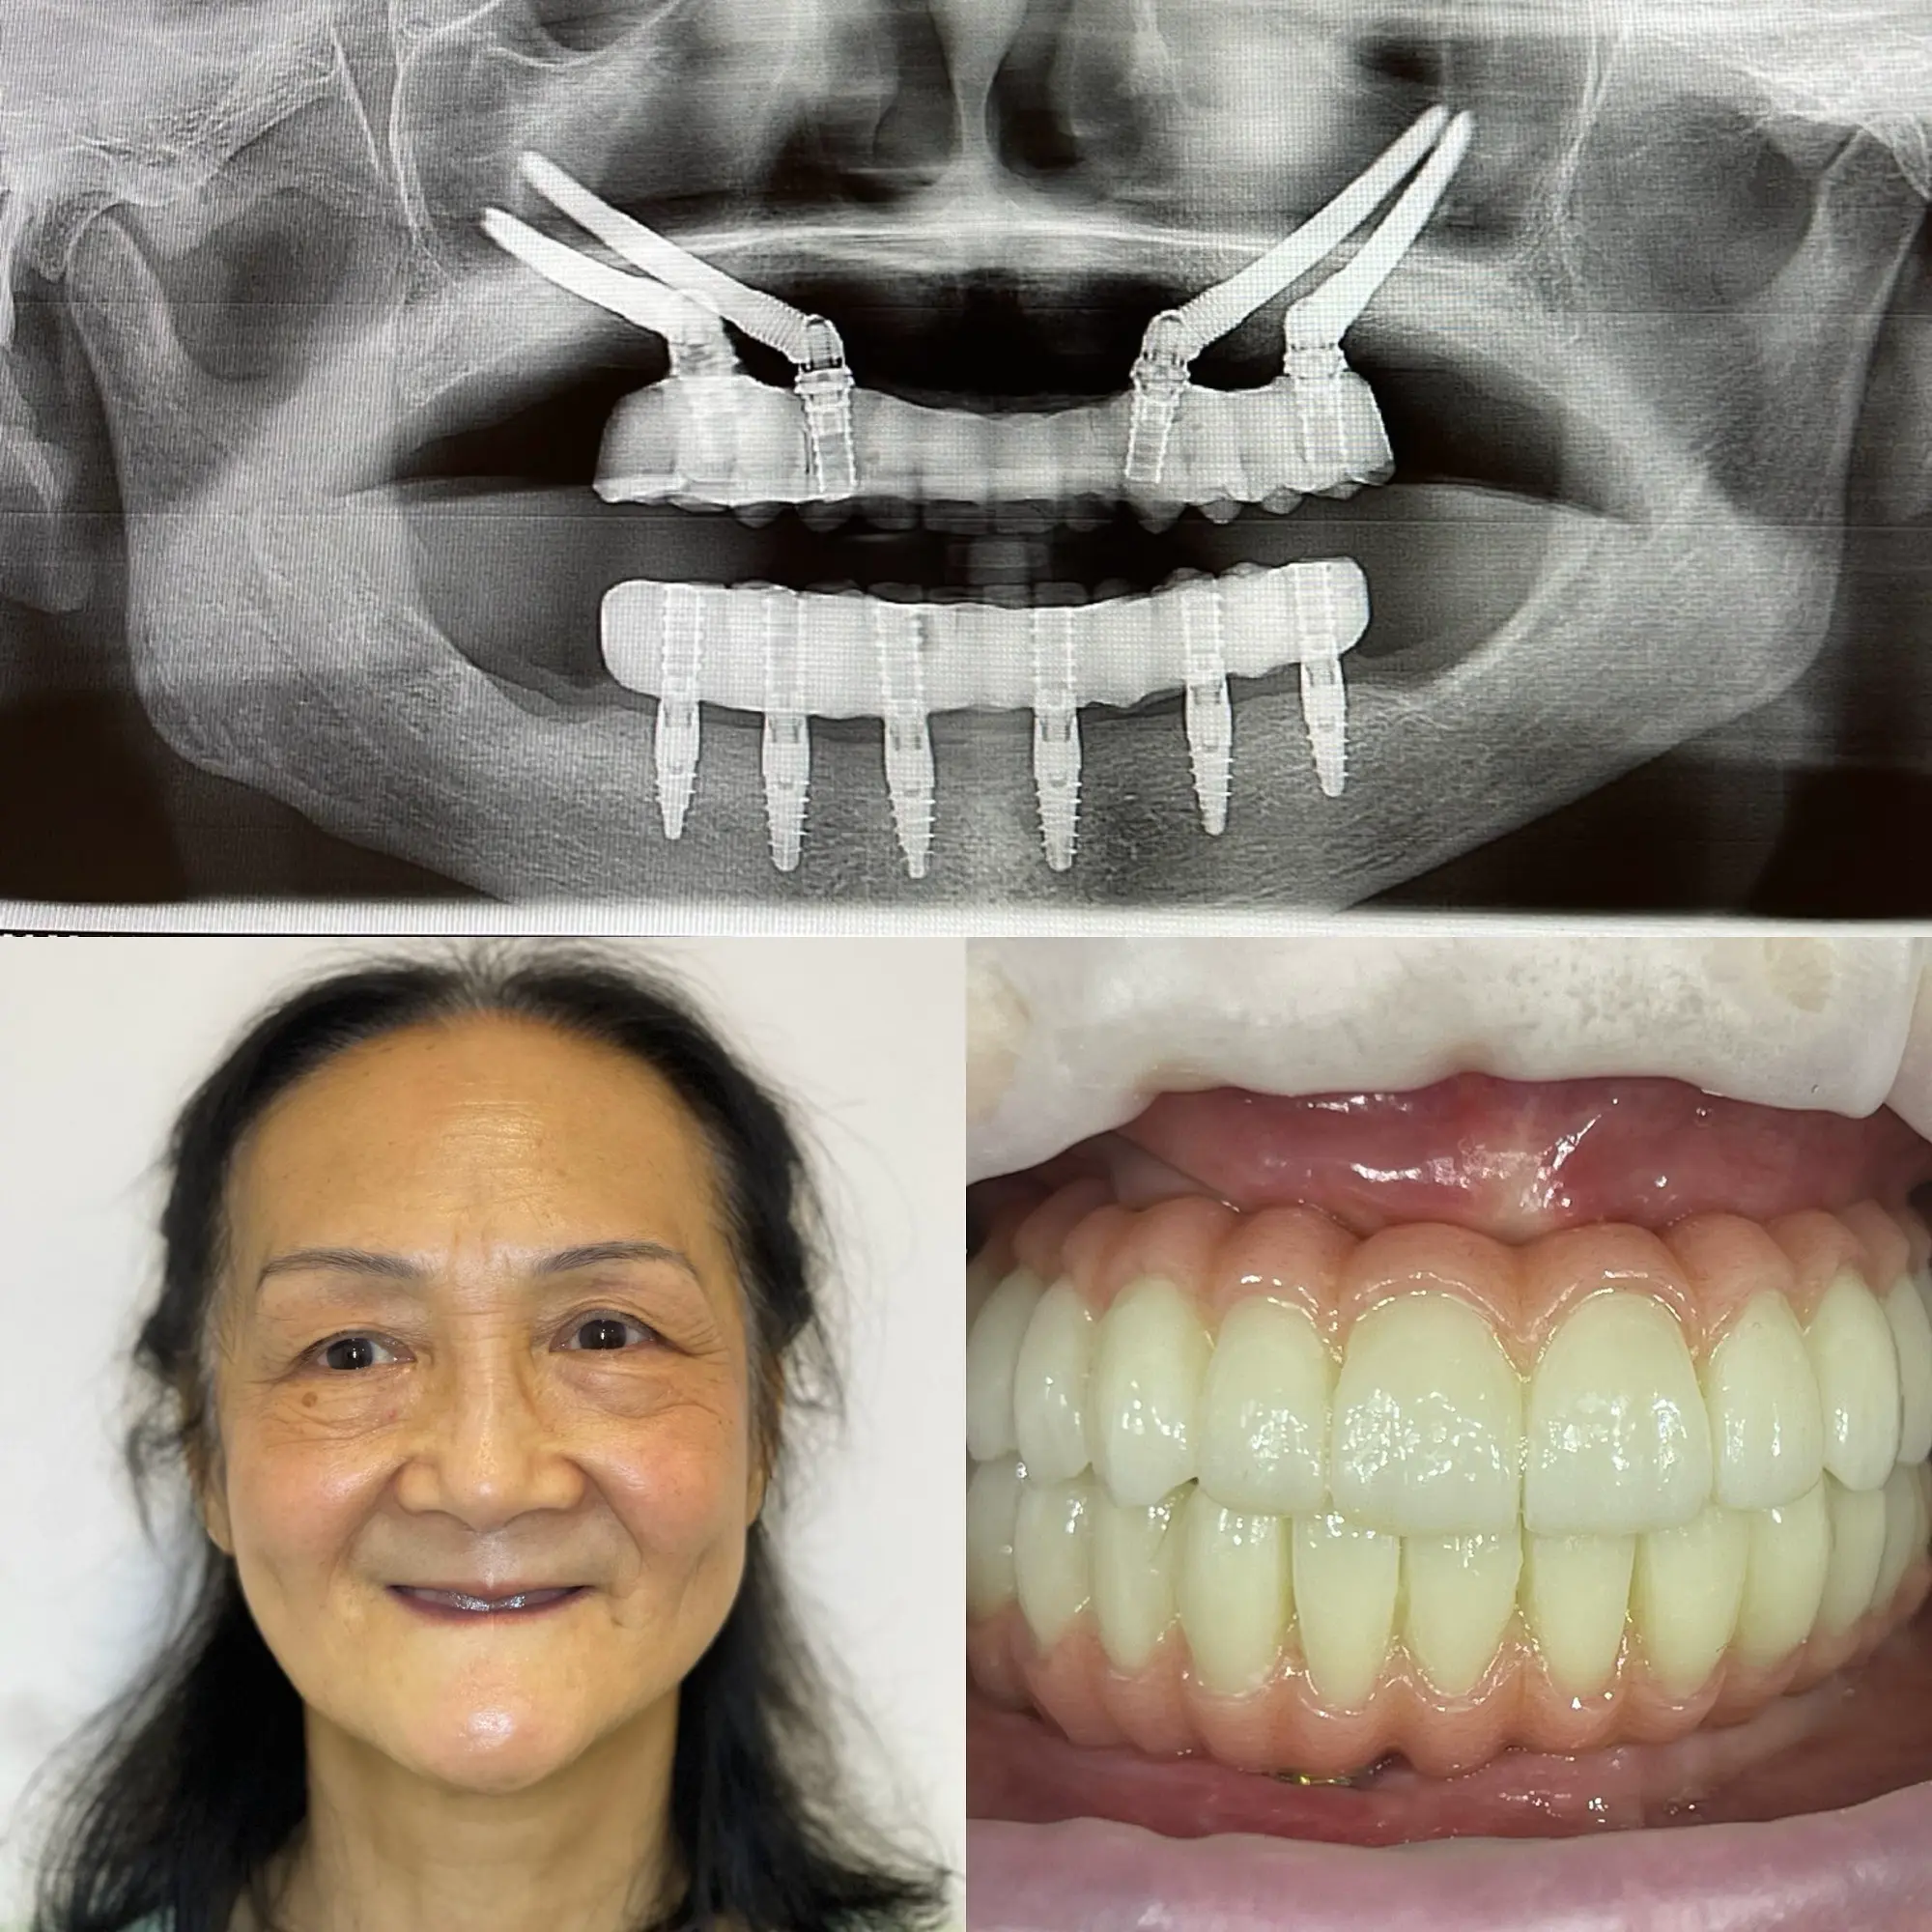

Dr Al-Hashemi is among the only few dentists offering Zygoma implants. Dr Hashemi has handled some of the most difficult dental implant cases and given beautiful smiles to his patients.

When you choose to have full mouth implants with us, you will leave on the same day with fixed teeth. We never provide temporary dentures. Proclinix Dental Implant Centre, designs and mills a bespoke, one-piece, screw-retained prosthesis from start to finish on the day of your surgery.